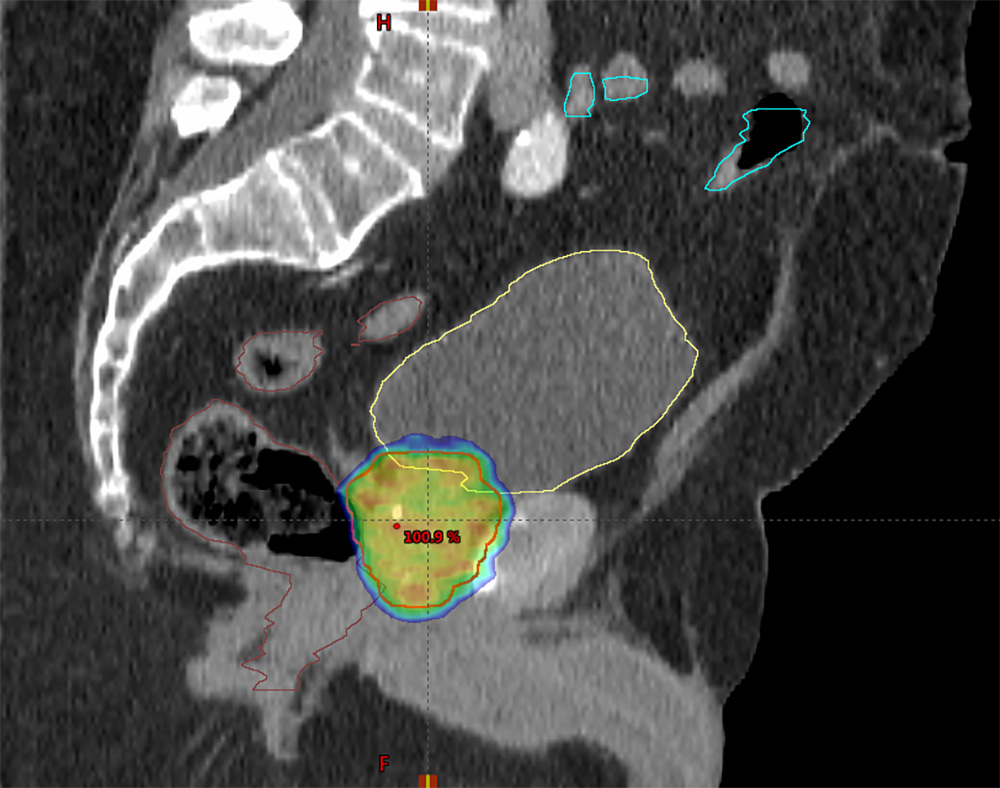

Den nye stråleteknikken innebærer at strålingen blir mer målrettet enn før, der vi kan skreddersy strålene til det vi ønsker å bestråle. På den måten klarer vi i større grad å spare friskt vev, og forhåpentligvis gir dette mindre bivirkninger enn den gamle stråleteknikken. Kurativ strålebehandling ved prostatakreft gis med én behandling daglig mandag til fredag, fordelt på 20 eller 35 behandlinger som strekker seg over enten fire eller syv uker. Langtidsoverlevelsen etter stråleterapi er svært god, der den kreftspesifikke overlevelsen 15 år etter behandling er på 85-90%.

Kurativ strålebehandling (helbredende behandling) ved prostatakreft hos nordnorske pasienter er sentralisert til Universitetssykehuset Nord-Norge (UNN) i Tromsø. Her strålebehandler vi årlig mer enn 120 menn med prostatakreft. Kirurgi kan gi ereksjonssvikt og urinlekkasje, mens strålebehandlingen kan gi bivirkninger i form av ereksjonssvikt, vannlatingsplager og endret avføringsmønster.